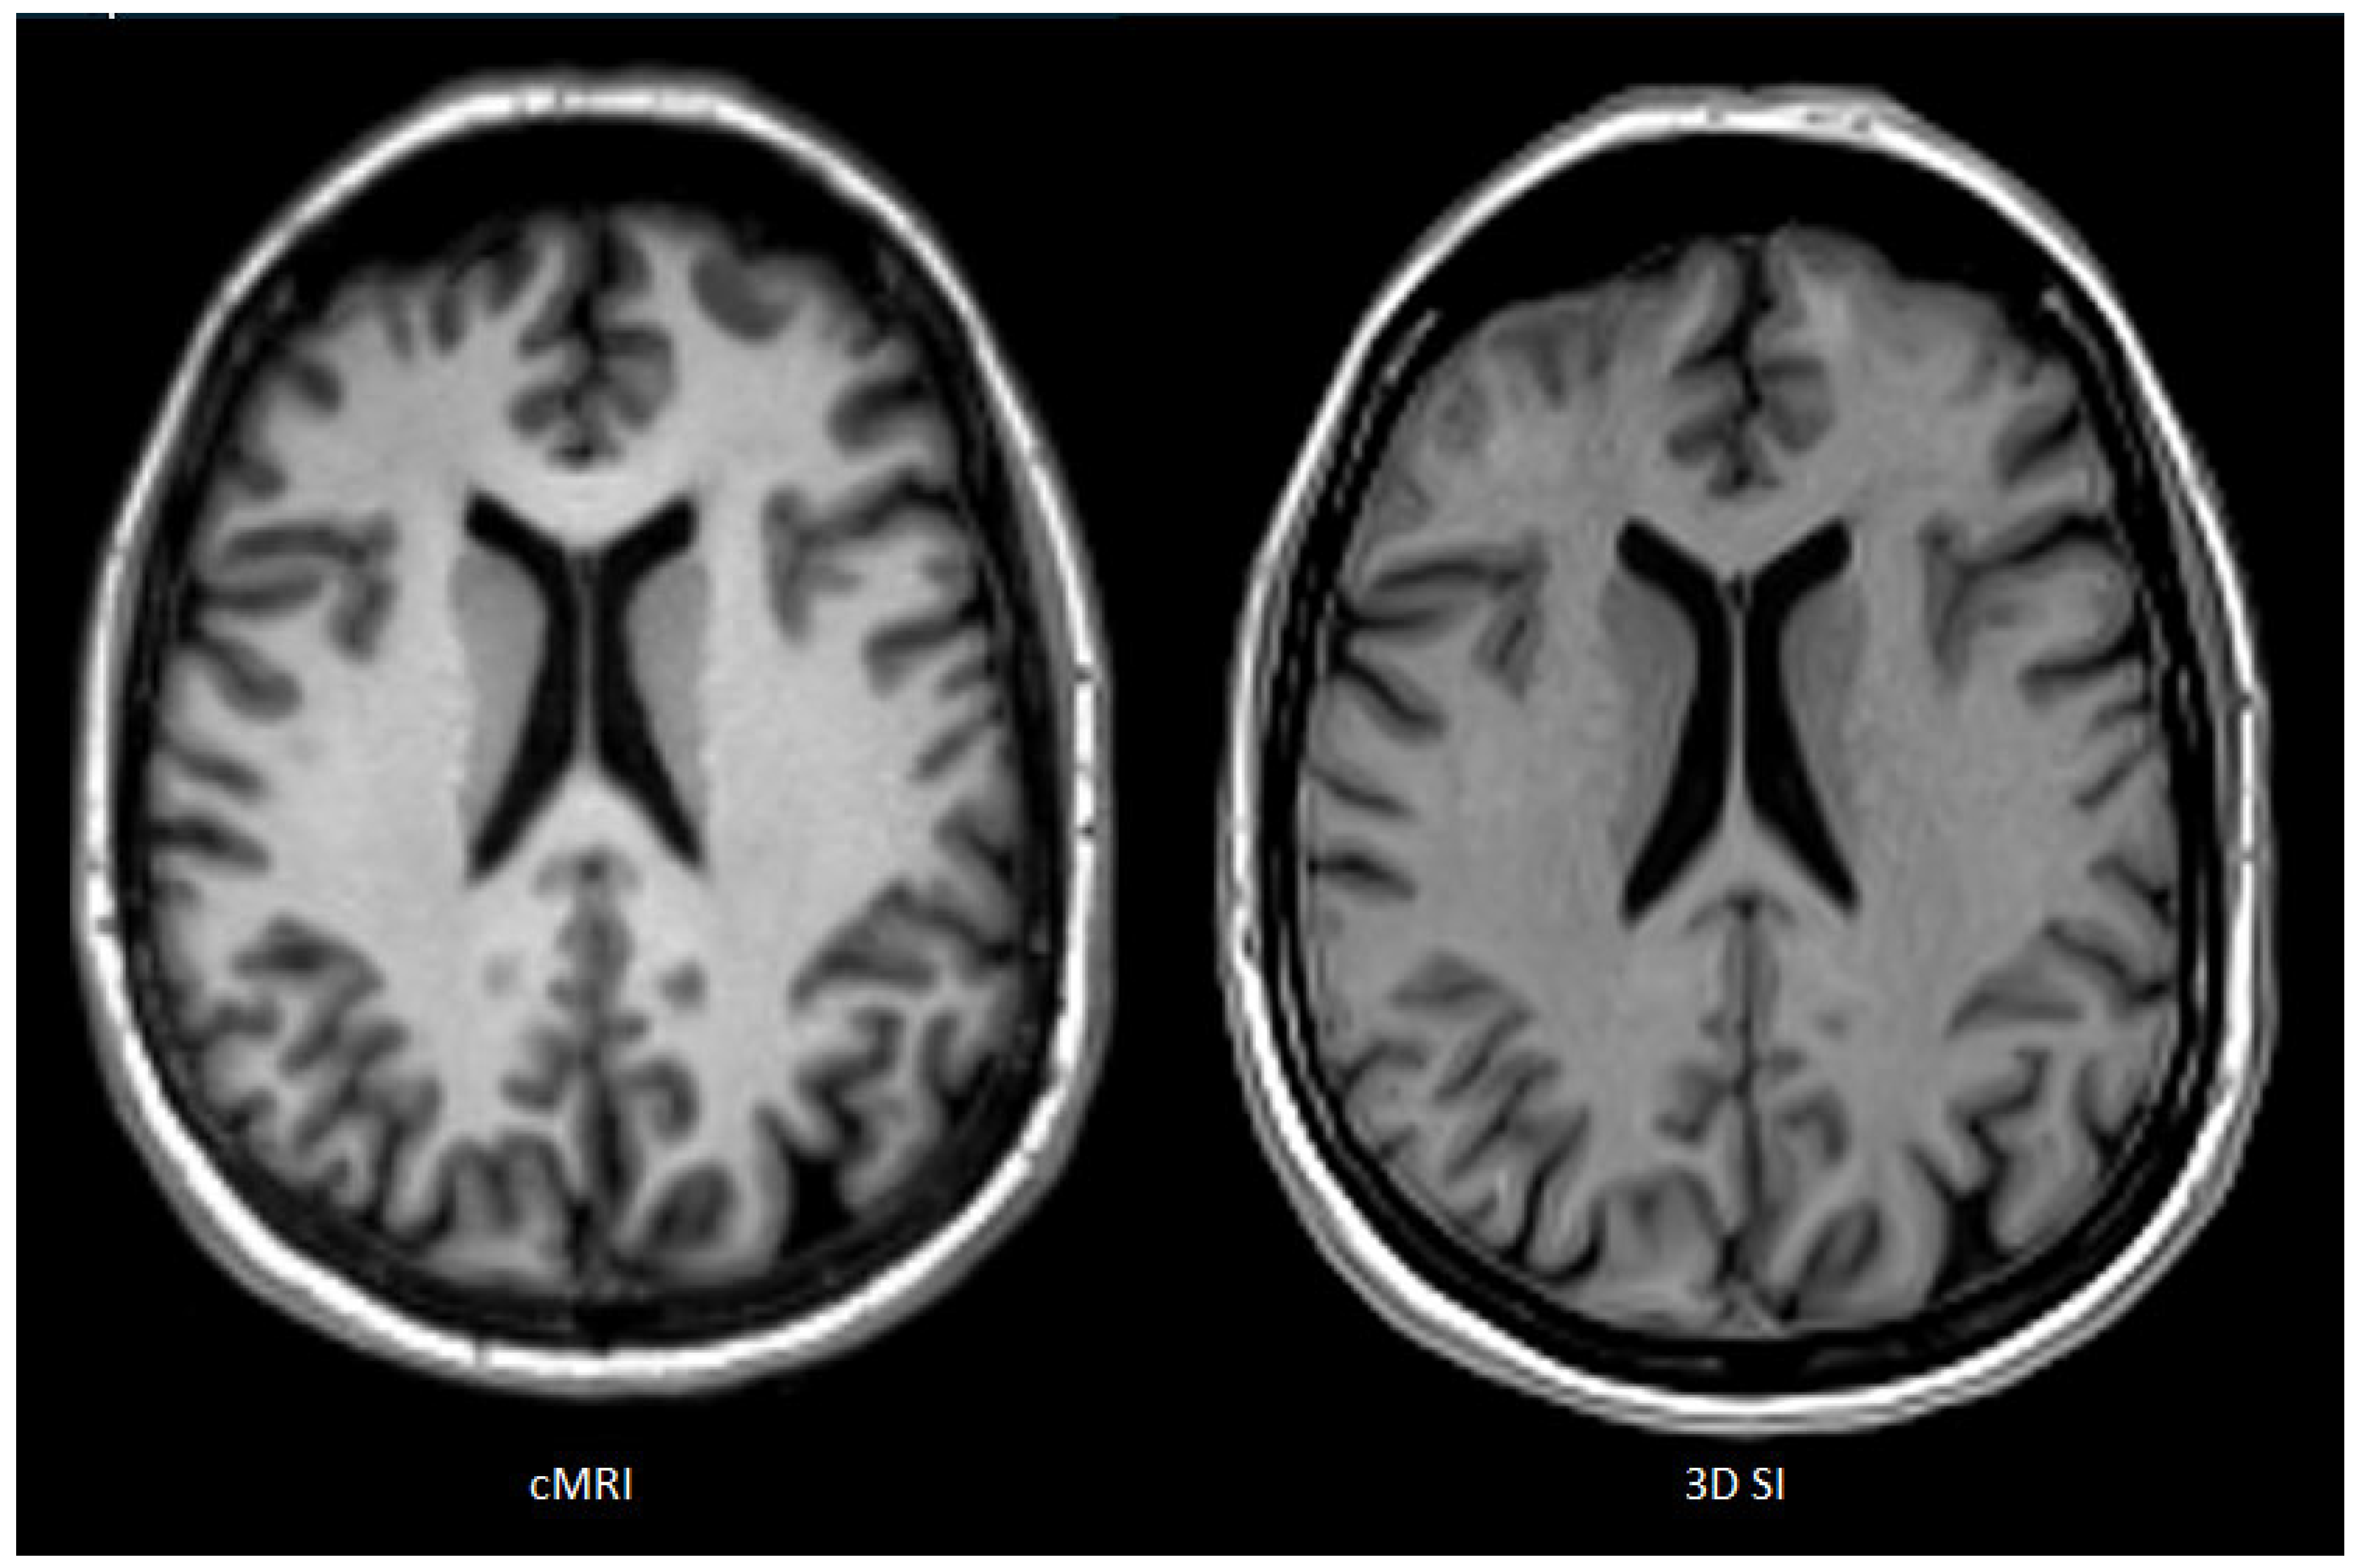

Figure 2 shows a slice of a single patient’s T1w images for each cMRI (left) and 3D SI (right) as an example for perceived SNR ratings: cMRI: R1, 87; R2, 91; R3, 76; and 3D SI: R1, 68; R2, 76; R3, 62.

Figure 2. Slice of a single patient’s T1w images for each cMRI and 3D SI as an example for perceived signal to noise (cMRI: R1, 87; R2, 91; R3, 76; and 3D SI: R1, 68; R2, 76; R3, 62).